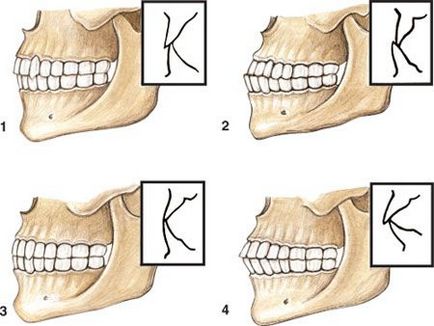

Normál restbite lehet bemutatni a különböző kiviteli alakoknál, különböző jellegű szorító. Meghívjuk Önt, hogy fontolja meg őket részletesen.

- Orthognathic. Az ilyen típusú lezárás tekinthető ideális. Ez az, ahol a felső sorban átfedi az alsó egyharmadát. Fontos, hogy ez az elrendezés a fogak szilárdan érintkezik egymással, és nem volt diastema, azaz rések között a metszőfogak.

- Progenichesky. Ez a fajta egy kicsit olyan, mint a záró mesialis anomália. A fő jellemzője a kis állkapcsot előre. Ebben az esetben a művelet az állkapocsízület nem törött.

- Direct. Az első fogak a felső és az alsó állkapocs az ilyen típusú szorító érintkeznek egymással. Kiderült, hogy az ívek párhuzamosan vannak elrendezve. Annak ellenére, hogy egy ilyen helyzetben tartják, hogy egy természetes fog, akkor vannak hátrányai. A legsúlyosabb - a gyors kopás a zománc, mivel van egy nagy terhelést a vágási felület a csont.

- Biprognatichesky. Ebben az esetben a kiterjesztés nem csak a felső, hanem az alsó állkapocs előre ajkát, miközben rendes érintkezés fogászati ryadov.Vse lehetőségek befogófogak látható a képen.

Fogazat az Ezen megvalósítási módok bármelyikében, egy teljesen működőképes. Továbbá, minden fajta rendelkezik esztétikus és harmonikus megjelenésű arcát.